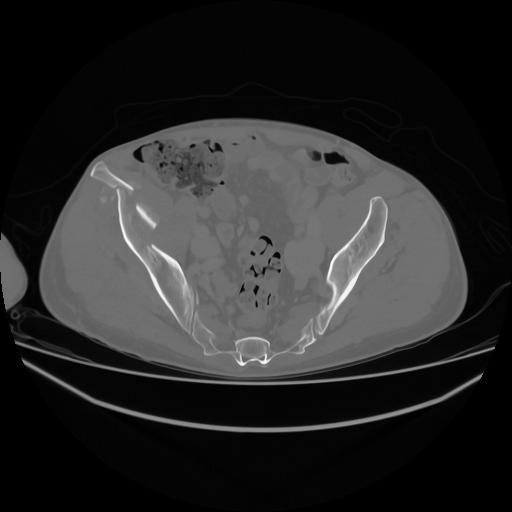

5 CUERPO,CE,Vol,1.0,CUERPO,,